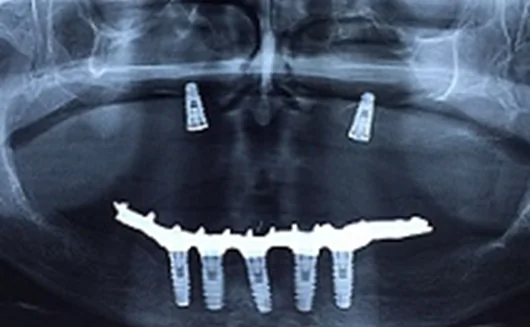

Paciente do sexo masculino, 51 anos, foi encaminhado ao Centro de Treinamento da DSp (Campo Largo, PR) com extrema mobilidade do incisivo superior esquerdo. O exame clínico evidenciou prótese dentária sem estabilidade devido à fratura de um remanescente dentário que serviu de auxílio adicional para este tipo de restauração. Foi sugerida a extração da raiz do dente remanescente e a instalação imediata do implante por meio da CN. Além disso, o preenchimento do GAP com biomaterial para manutenção do contorno gengival e restauração estética também foi planejado.

O fluxo de trabalho atual da CN consiste em: (1) O sistema DICOM foi gerado com fiduciais e inserido no Sistema de Imagens DSP com o objetivo de realizar o planejamento virtual (2). Uma tala de plano oclusal foi instalada na arcada superior com auxílio de silicone. Esta tala é pré-calibrada com 4 esferas metálicas que servem para conciliar o planejamento virtual com a posição da broca em tempo real na arcada interessada durante a cirurgia. Um sensor de localização do paciente é instalado na câmera para completar a leitura e cruzar os dados entre o sensor e a peça de mão, gerando uma réplica virtual do que está acontecendo em tempo real (3). Após o correto posicionamento das 4 esferas, o sistema demonstrou um “S” na cor verde indicando que o registro estava calibrado, ou seja, os pontos virtuais coincidiam com os reais e, em seguida, o implante foi instalado (4).